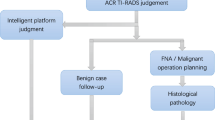

An artificial intelligence (AI) algorithm based on convolutional neural networks was used in ultrasound diagnosis in order to evaluate its performance in judging the nature of thyroid nodules and nodule classification.

A total of 105 patients with thyroid nodules confirmed by surgery or biopsy were retrospectively analyzed. The properties, characteristics, and classification of thyroid nodules were evaluated by sonographers and by AI to obtain combined diagnoses. Receiver operating characteristic curves were generated to evaluate the performance of AI, the sonographer, and their combined effort in diagnosing the nature of thyroid nodules and classifying their characteristics. In the diagnosis of thyroid nodules with solid components, hypoechoic appearance, indistinct borders, Anteroposterior/transverse diameter ratio > 1(A/T > 1), and calcification performed by sonographers and by AI, the properties exhibited statistically significant differences.

Sonographers had a sensitivity of 80.7%, specificity of 73.7%, accuracy of 79.0%, and area under the curve (AUC) of 0.751 in the diagnosis of benign and malignant thyroid nodules. AI had a sensitivity of 84.5%, specificity of 81.0%, accuracy of 84.7%, and AUC of 0.803. The combined AI and sonographer diagnosis had a sensitivity of 92.1%, specificity of 86.3%, accuracy of 91.7%, and AUC of 0.910.

The efficacy of a combined diagnosis for benign and malignant thyroid nodules is higher than that of an AI-based diagnosis alone or a sonographer-based diagnosis alone. The combined diagnosis can reduce unnecessary fine-needle aspiration biopsy procedures and better evaluate the necessity of surgery in clinical practice.